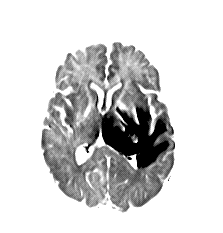

We introduce a neural network framework, utilizing adversarial learning to partition an image into two cuts, with one cut falling into a reference distribution provided by the user. This concept tackles the task of unsupervised anomaly segmentation, which has attracted increasing attention in recent years due to their broad applications in tasks with unlabelled data. This Adversarial-based Selective Cutting network (ASC-Net) bridges the two domains of cluster-based deep learning methods and adversarial-based anomaly/novelty detection algorithms. We evaluate this unsupervised learning model on BraTS brain tumor segmentation, LiTS liver lesion segmentation, and MS-SEG2015 segmentation tasks. Compared to existing methods like the AnoGAN family, our model demonstrates tremendous performance gains in unsupervised anomaly segmentation tasks. Although there is still room to further improve performance compared to supervised learning algorithms, the promising experimental results shed light on building an unsupervised learning algorithm using user-defined knowledge.